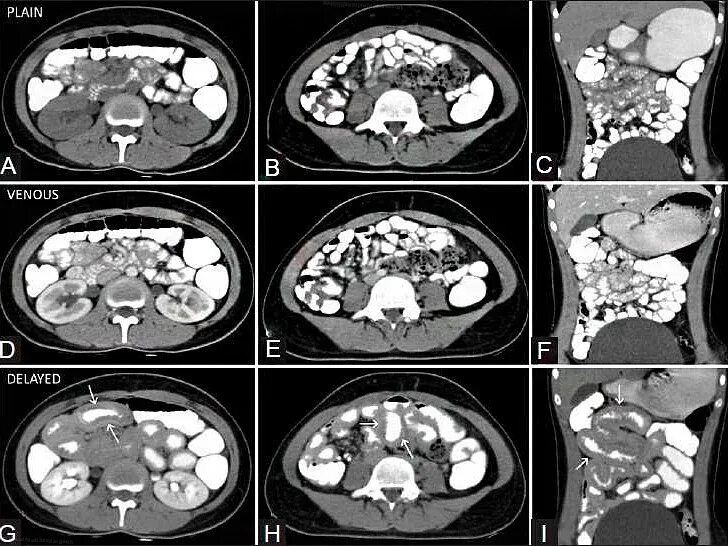

Мрт обп с контрастированием